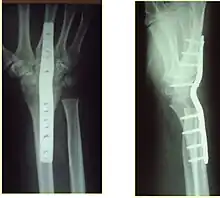

The techniques of surgical management include open reduction internal fixation (ORIF), external fixation, percutaneous pinning, or some combination of the above. The choice of operative treatment is often determined by the type of fracture, which can be categorized broadly into three groups: partial articular fractures, displaced articular fractures, and metaphyseal unstable extra- or minimal articular fractures.[4]

Significant advances have been made in ORIF treatments. Two newer treatment are fragment-specific fixation and fixed-angle volar plating. These attempt fixation rigid enough to allow almost immediate mobility, in an effort to minimize stiffness and improve ultimate function; no improved final outcome from early mobilization (prior to 6 weeks after surgical fixation) has been shown. Although restoration of radiocarpal alignment is thought to be of obvious importance, the exact amount of angulation, shortening, intra-articular gap/step which impact final function are not exactly known. The alignment of the DRUJ is also important, as this can be a source of a pain and loss of rotation after final healing and maximum recovery.

If the fractures are unlikely to be reduced by closed means, open reduction with internal plate fixation is preferred.[4] Although major complications (i.e. tendon injury, fracture collapse, or malunion) result in higher reoperation rates (36.5%) compared to external fixation (6%), ORIF is preferred, as this provides better stability and restoration of the volar tilt.[4][20] Following the operation, a removable splint is placed for 2 weeks, during which time patients should mobilize the wrist as tolerated.[4]